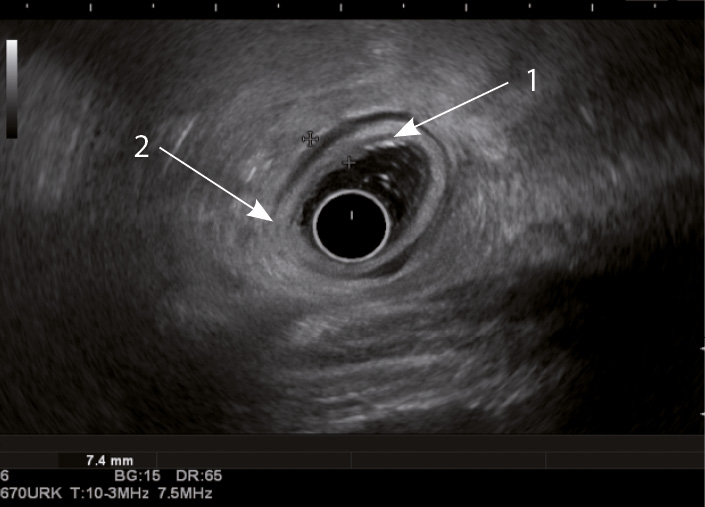

Рис. 3. Эндосонографическая картина толстой кишки при язвенном колите; 1 – утолщение слизисто-подслизистого слоя; 2 – утолщение стенки толстой кишки

Кишечная стенка статистически значимо чаще утолщалась за счет слизисто-подслизистого слоя при ЯК, чем при БК: в 82 и 7,14% соответственно; диагностическая чувствительность данного признака была 82%, а специфичность – 93% (табл. 1). При БК изменение стенки толстой кишки за счет трансмурального утолщения выявлялось статистически значимо чаще (68%), чем при ЯК (9%) (чувствительность 68%, специфичность 91%). Статистически значимых различий в частоте изменений мышечного слоя кишки отмечено не было. Только при БК в 68% случаев отсутствовала дифференцировка слоев кишечной стенки в фазе обострения (чувствительность и специфичность признака составили 68 и 100% соответственно) (см. рис. 4). При ЯК на фоне «смазанности» слизисто-подслизистого слоя у всех больных можно было визуализировать мышечный и серозный слои (см. табл. 1, рис. 3).